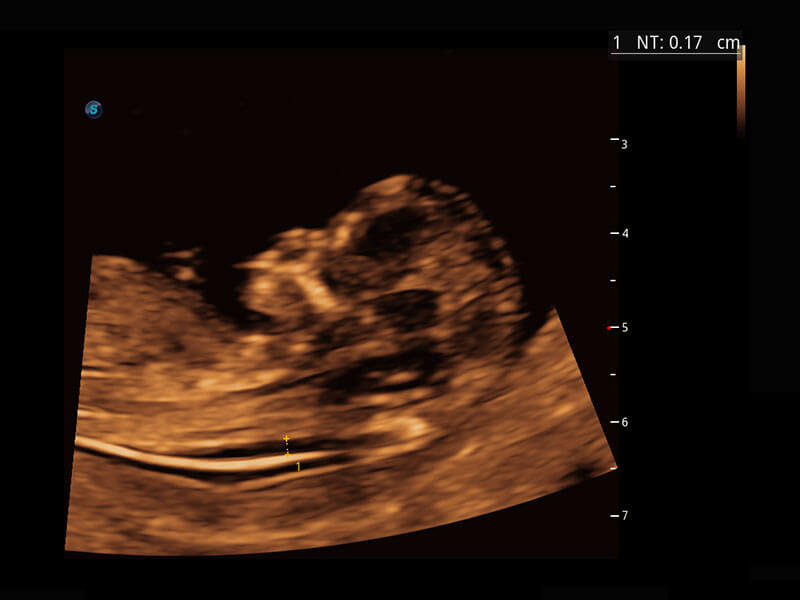

P60在胎儿早孕期超声筛查中为您带来优异的图像质量。

高分辨率容积成像-早孕胎儿